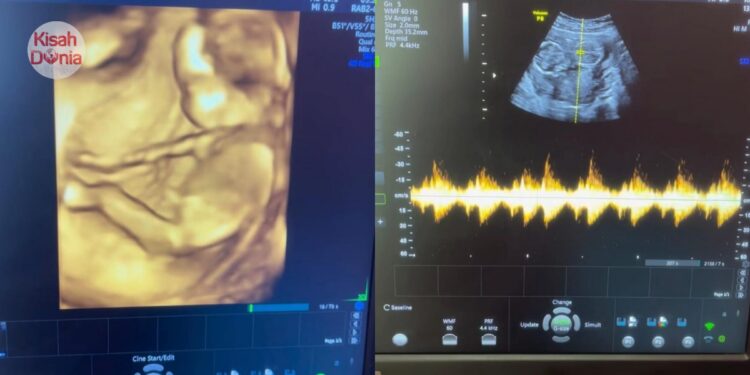

Baru-baru ini, seorang Pakar Obgyn sempat berkongsikan lakonan semula ketika dia mengendalikan sesi pemeriksaan bersama seorang pelajar sekolah menengah. Gadis itu hadir ditemani ibunya dengan keluhan sudah lama tidak didatangi haid. Sudah menjadi prosedur biasa, golongan wanita yang mengalami masalah melibatkan kewanitaan pastinya akan melalui proses imbasan perut.

Sebelum ini, si ibu memaklumkan bahawa gangguan kitaran haid tersebut berkemungkinan berlaku akibat tekanan yang dialami anaknya selepas memulakan sesi persekolahan di sekolah menengah. Namun siapa sangka, hasil imbasan USG mendedahkan kewujudan janin yang telah terbentuk sempurna di dalam rahim remaja itu. Dalam erti kata lain, anaknya disahkan hamil luar nikah.